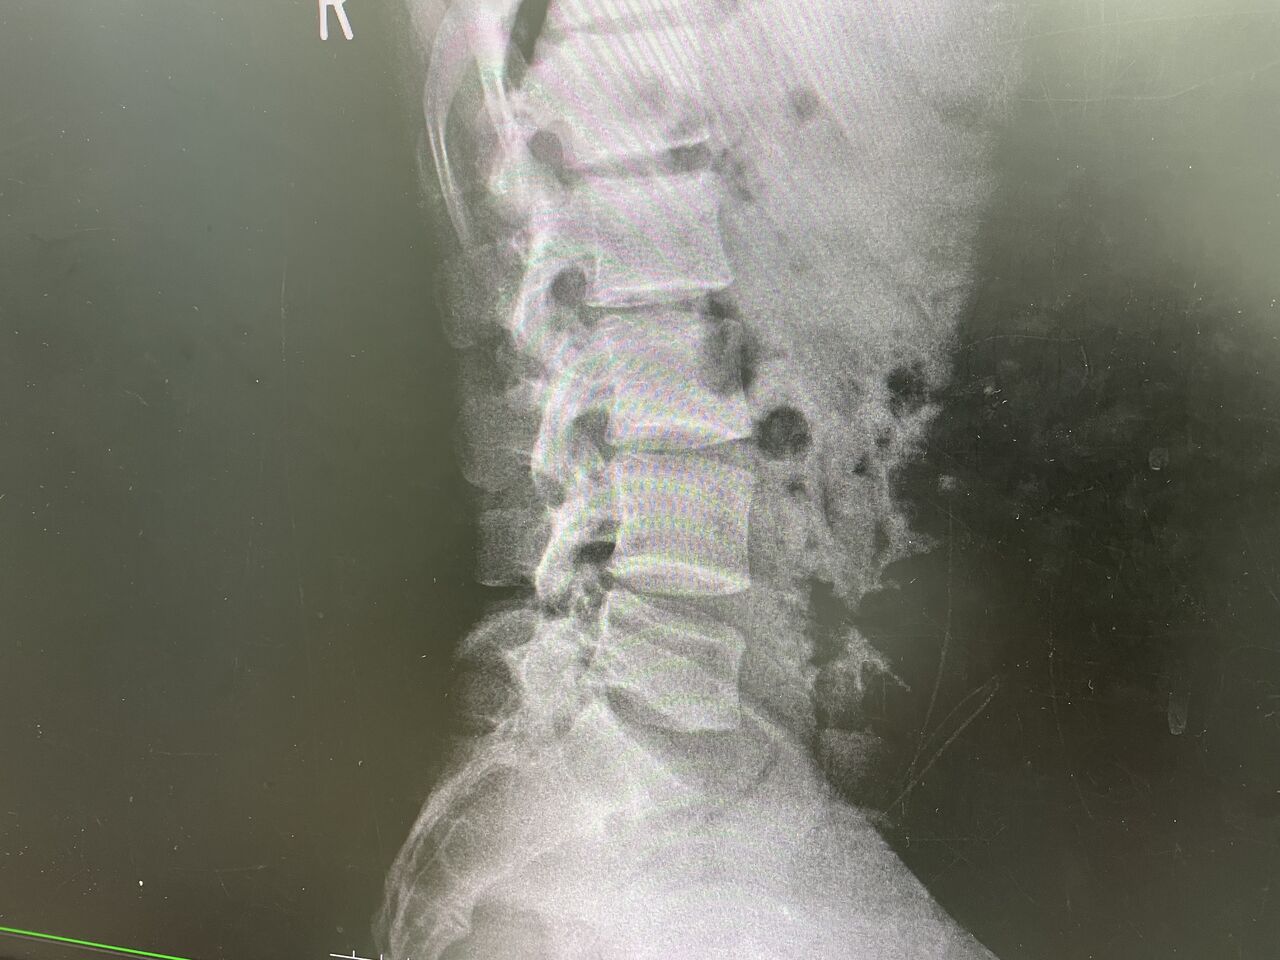

背部の痛みを取れなくて、来院